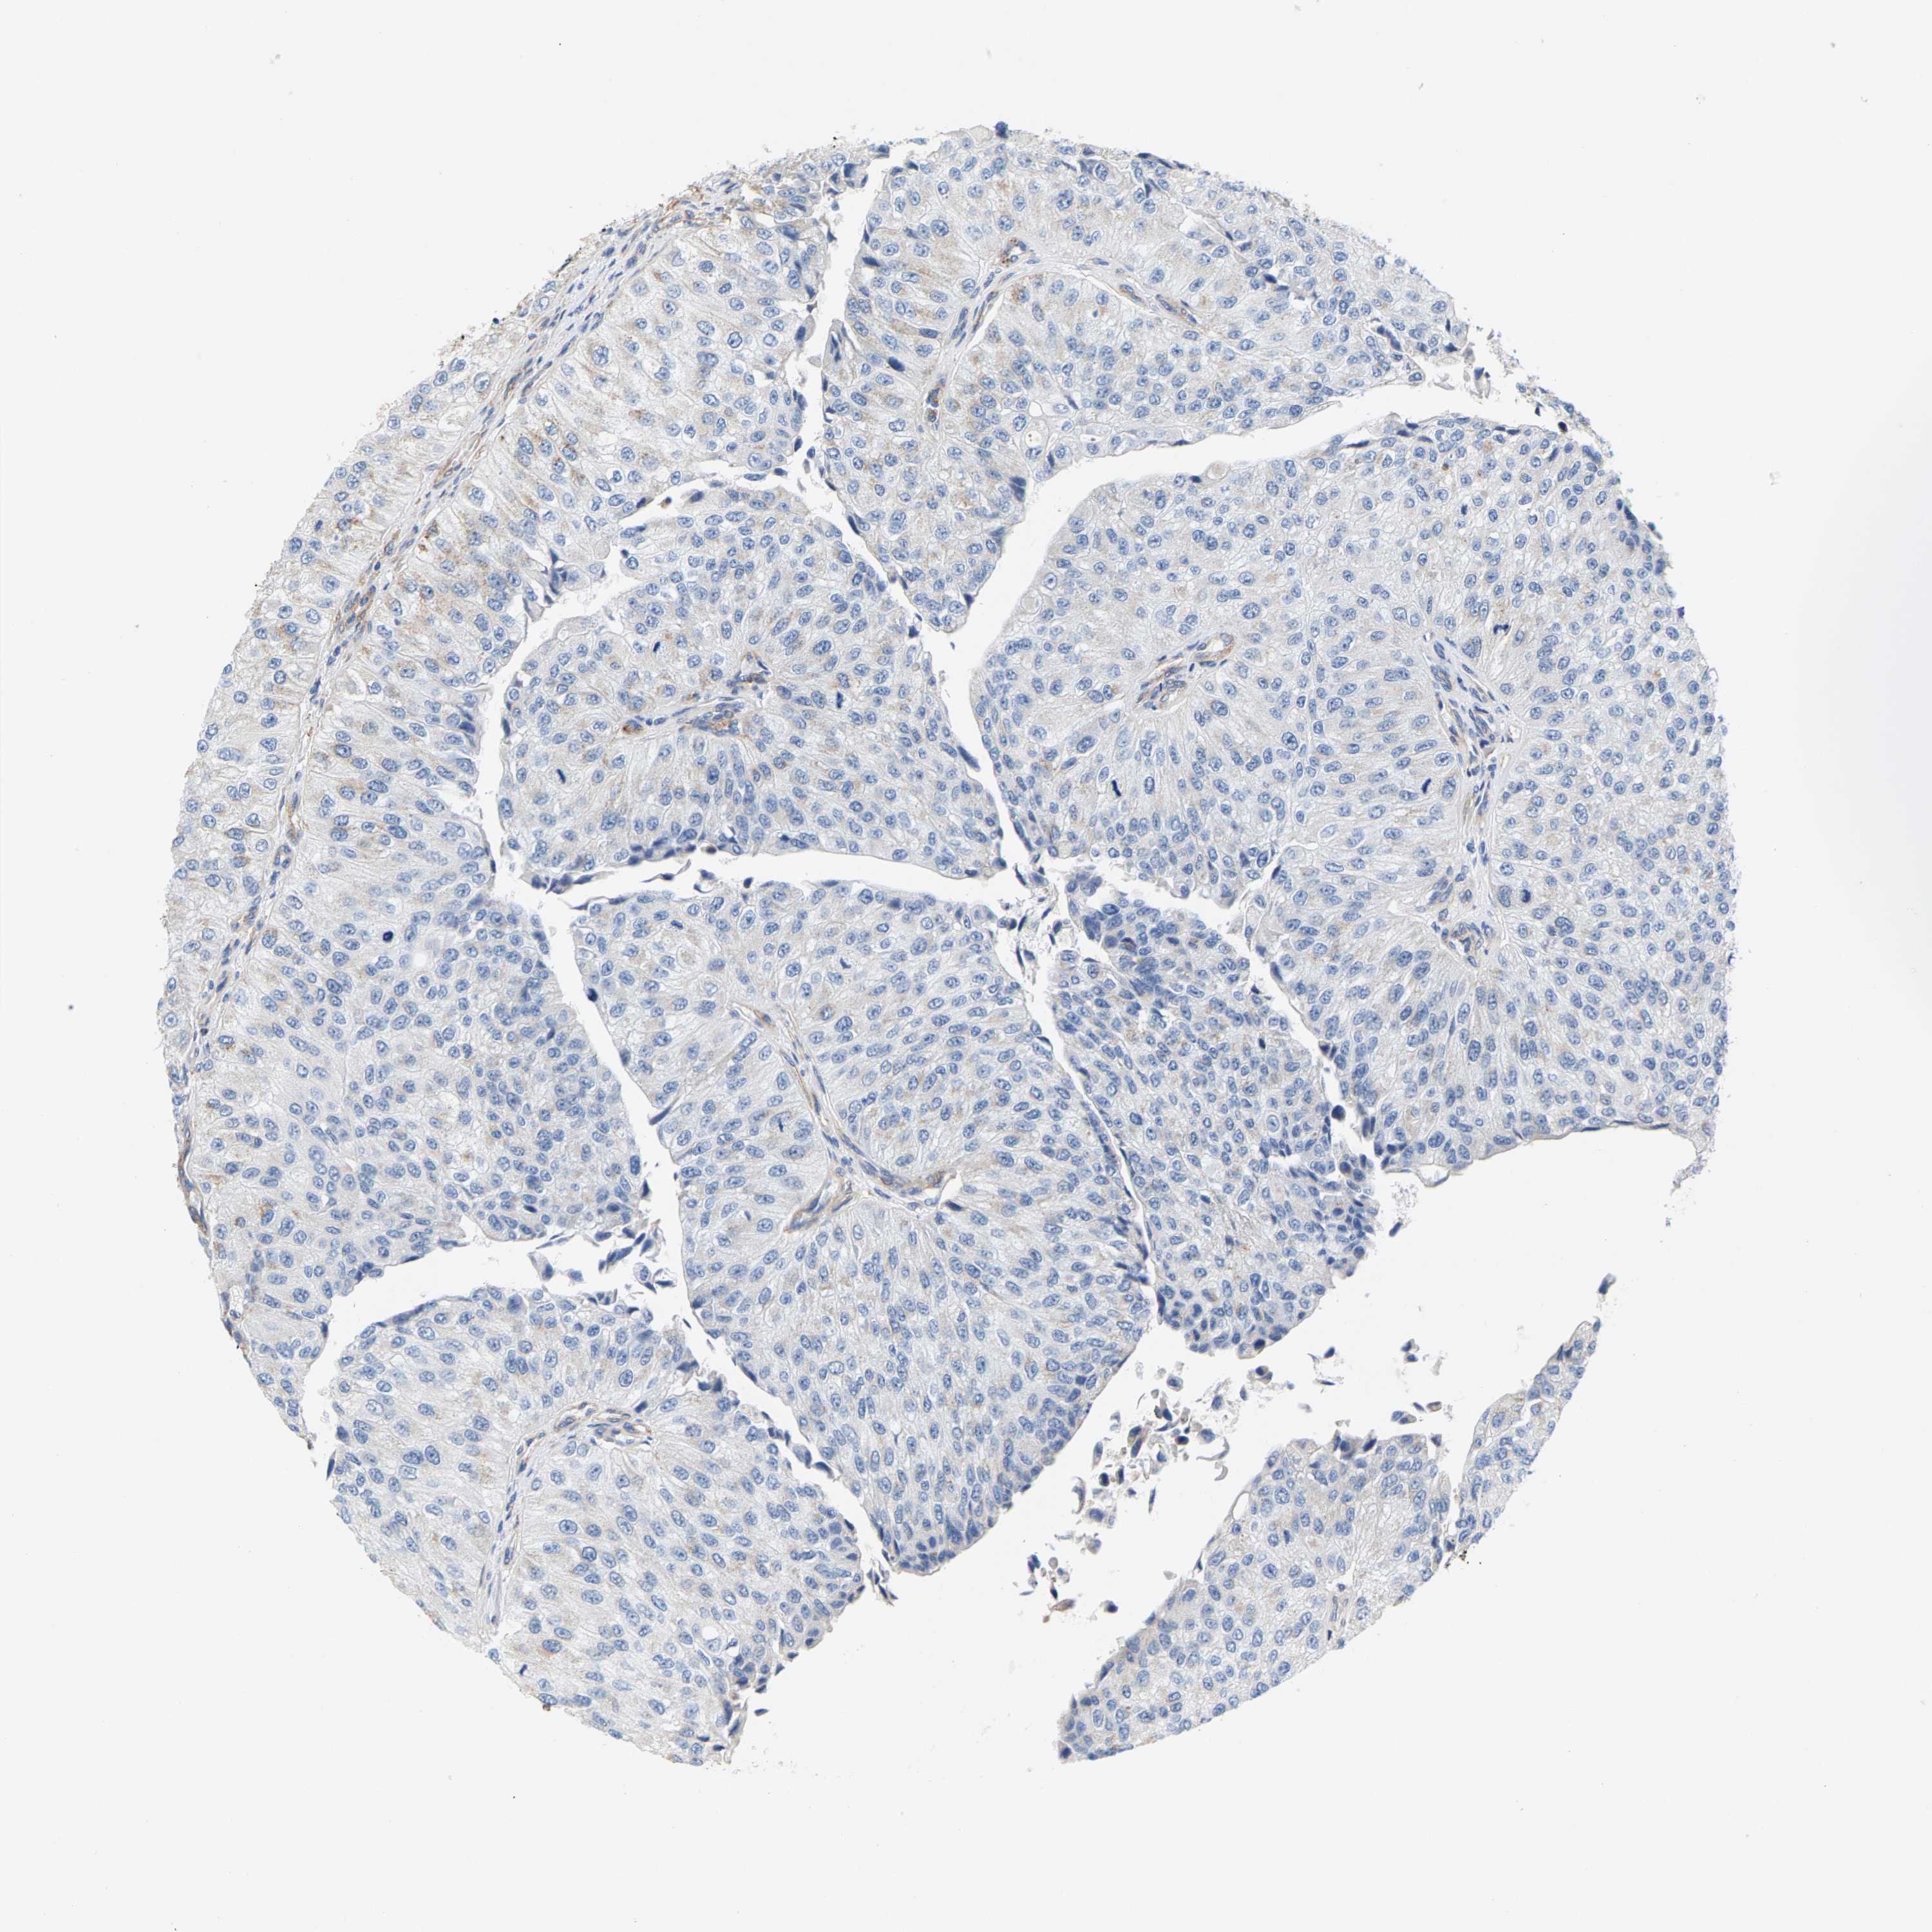

UROTHELIAL CANCER - Protein expressioni

A mouse-over function shows sample information and annotation data. Click on an image to view it in a full screen mode. Samples can be filtered based on level of antibody staining by selecting one or several of the following categories: high, medium, low and not detected. The assay and annotation is described here.

Antibody stainingi

Antibody staining in the annotated cell types in the current human tissue is reported as not detected, low, medium, or high, based on conventional immunohistochemistry profiling in selected tissues. This score is based on the combination of the staining intensity and fraction of stained cells.

Each image is clickable and will lead to virtual microscopy that enables deeper exploration of all samples and also displays staining intensity scores, fraction scores and subcellular localization as well as patient and tissue information for each sample.

Antibody HPA020543

Antibody HPA020549

Staining

High

Medium

Low

Not detected

Intensity

Strong

Moderate

Weak

Negative

Quantity

>75%

75%-25%

<25%

None

Location

Nuclear

Cytoplasmic/membranous

Cytoplasmic/membranous,nuclear

Urothelial carcinoma, Low grade

Urothelial carcinoma, High grade